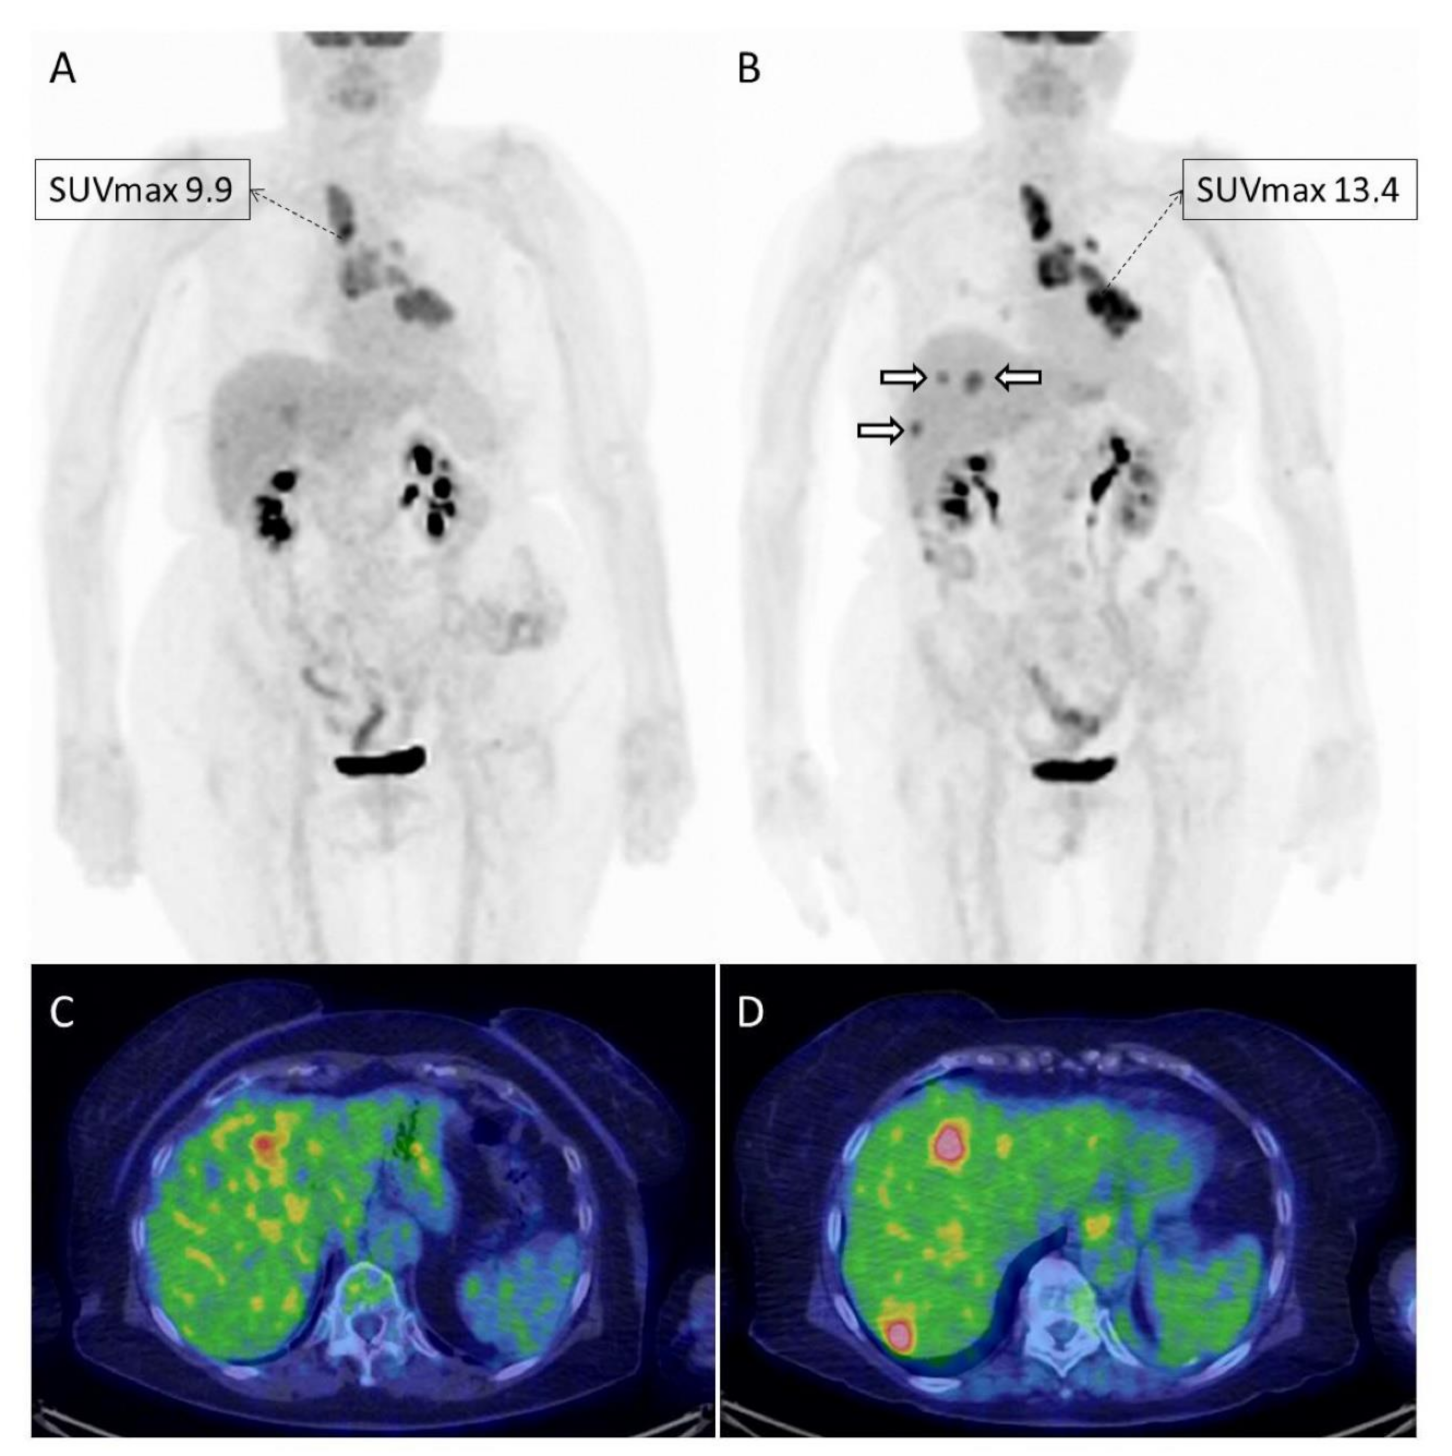

| Humbert et al. | 2020 | prospective | NSCLC | 50 | nivolumab, ipilimumab | PERCIST | Pseudoprogression and iDR (immune dissociated-response) associated with clinical benefit | [30] |

| Castello et al. | 2020 | prospective | NSCLC | 46 | nivolumab, ipilimumab pembrolizumab | SUVmax, SUVmean, MTV, TLG | Baseline MTV and dNLR predictors for hyperprogression | [28] |